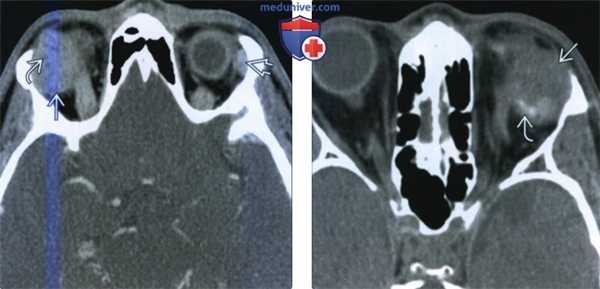

(Слева) При КТ с КУ в аксиальной проекции определяется несколько гетерогенное контрастное объемное образование с четкими контурами. В ткани опухоли часто обнаруживается мелкая киста. Обратите внимание на неизмененную контрлатеральную слезную железу.

(Справа) При аксиальной КТ без контрастного усиления определяется дольчатое объемное образование левой слезной железы с четкими контурами, содержащее в своей задней части кальцинаты. (Слева) При корональной КТ без контрастного усиления в верхневисочном отделе левой глазницы определяется дольчатое объемное образование, сопровождающееся «фестончатой» перестройкой кости ямки слезной железы. Обратите внимание на характерное смещение глазного яблока, вызываемое опухолями области слезной железы.

(Справа) При МРТ Т1 с КУ в корональной проекции в верхнелатеральной части левой глазницы визуализируется контрастируемое объемное образование с четкими контурами, вызывающее ровную «фестончатую» перестройку кости.

(Справа) При аксиальной КТ без контрастного усиления определяется дольчатое объемное образование левой слезной железы с четкими контурами, содержащее в своей задней части кальцинаты.

(Слева) При корональной КТ без контрастного усиления в верхневисочном отделе левой глазницы определяется дольчатое объемное образование, сопровождающееся «фестончатой» перестройкой кости ямки слезной железы. Обратите внимание на характерное смещение глазного яблока, вызываемое опухолями области слезной железы.